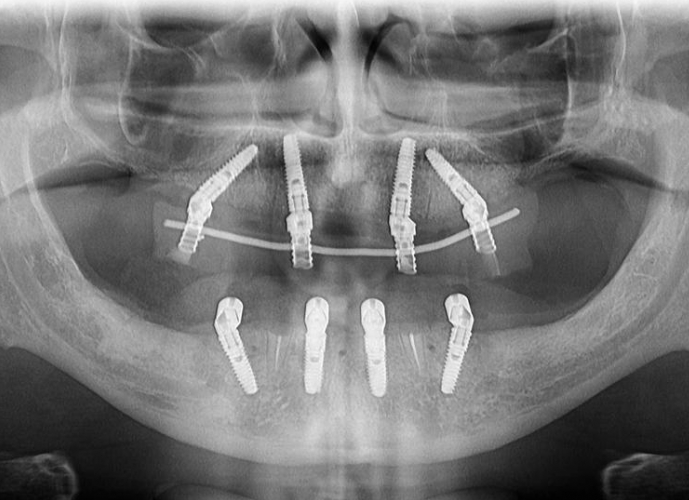

Vă prezentăm un caz All-on-4 finalizat cu succes cu ajutorul a 2 ghiduri chirurgicale realizate 100% cu ajutorul tehnologiei digitale.

Am folosit doua ghiduri: unul pentru osteoplastia crestei alveolare, iar cel de-al doilea pentru inserarea implanturilor.